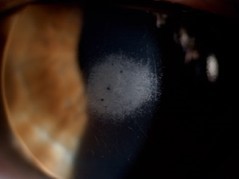

Aquesta edició se centra en la contactologia clínica

També hi ha disponibles per l’ortoqueratologia, l’adaptació de lents de contacte i el subministrament de lents de contacte (sense adaptació)